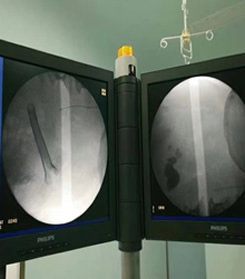

高锐副主任医师带领泌尿外科医护人员开展“首例输尿管软镜下肾结石碎石取石术”

据悉,在帮扶期间,高锐同志积极带领泌尿外科医护人员开展新技术、新业务,开创了5项固原市“首例”手术:输尿管软镜下肾结石碎石取石术、经皮肾镜复杂性肾结石碎石取石术、腹腔镜下结核肾切除术、阴茎癌根治术+腹腔镜下双侧腹股沟淋巴结清扫术、输尿管狭窄高压球囊扩张术,使原州区人民医院泌尿外科诊疗技术水平跃居榜首,得到了同行们的肯定。